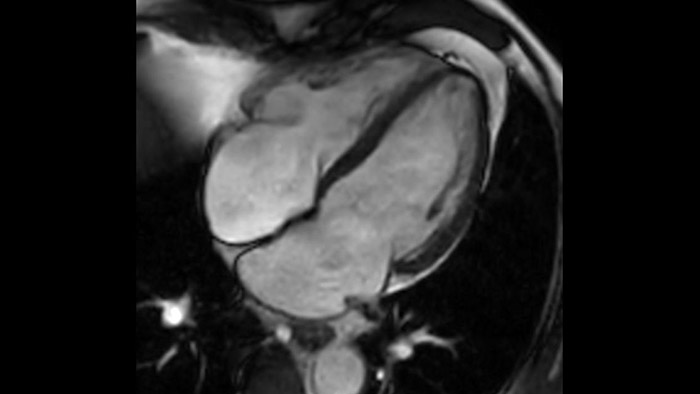

Comprehensive cardiac MR imaging

Diagnostic and prognostic utility of cardiac MR is increasing. Assess the anatomy and function of the heart using cine acquisitions, acquire information about perfusion and viability of the cardiac tissue, visualise potential edema with black blood sequence, access and even quantify tissue characterisation with CardiacQuant.